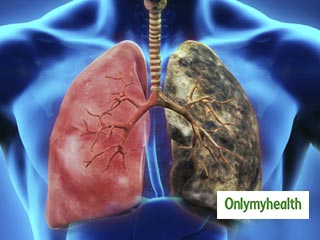

फेफड़ों का कैंसर (Lung Cancer) दुनिया भर में पुरुषों में होने वाला सबसे आम कैंसर था, 2018 में डाइग्‍नोज किए गए नए मामलों की कुल संख्या का 15.5% योगदान करते हैं। मुख्‍य रूप से तीन- फेफड़े, प्रोस्टेट और कोलोरेक्टल कैंसर, सभी कैंसर का 44.4% योगदान करते हैं (गैर-मेलेनोमा त्वचा कैंसर को छोड़कर)। इन आंकड़ों में 5% से अधिक योगदान देने वाले अन्य सामान्य कैंसर पेट और लिवर थे।

• फेफड़े का कैंस (20.9 लाख मामले)

• फेफड़े का कैंसर (17.6 लाख मौतें)